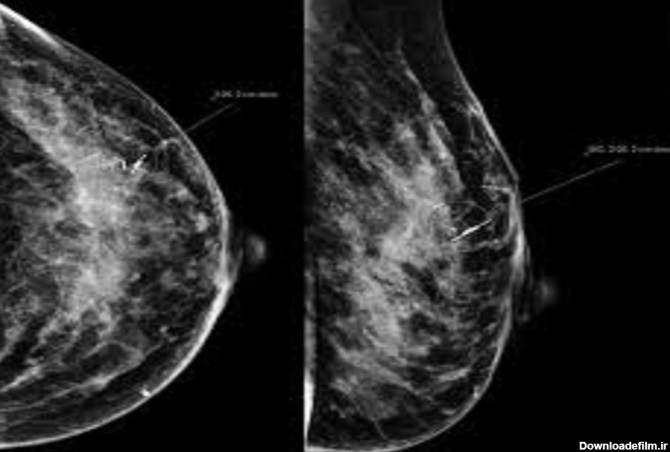

پستان نگاری یا ماموگرافی (Mammography) گونهای روش پرتونگاری است که در علوم تصویربرداری پزشکی

ماموگرافی، تصویربرادی از سینه و از مهمترین ارکان تشخیص سرطان سینه یا هر بیماری سینه است. این سرطان بین خانمها شایع است و باید مرتب سلامت سینه را چک کرد.

عکس ماموگرافی سالم ؛ماموگرافی یک فیلم اشعه ایکس پستان است که بادوز پایین برای تشخیص ناهنجاریهایی درپستان که خیلی کوچک هستند.